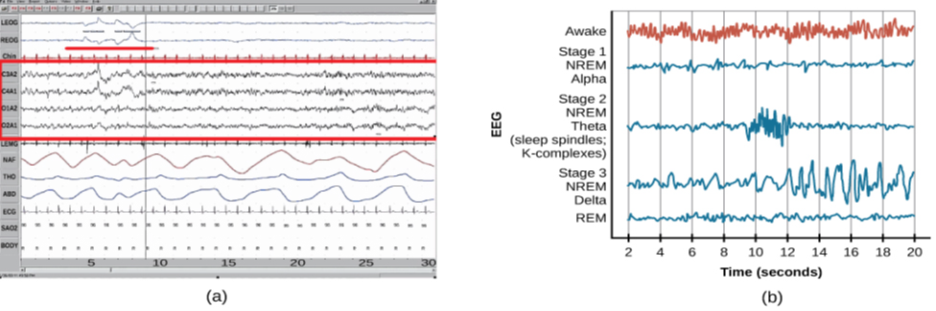

Sleep is not a uniform state of being. Instead, sleep is composed of several different stages that can be differentiated from one another by the patterns of brain wave activity that occur during each stage. These changes in brain wave activity can be visualized using EEG and are distinguished from one another by both the frequency and amplitude of brain waves (Figure 4.7). Sleep can be divided into two different general phases: REM sleep and non-REM (NREM) sleep. Rapid eye movement (REM) sleep is characterized by darting movements of the eyes under closed eyelids. Brain waves during REM sleep appear very similar to brain waves during wakefulness. In contrast, non-REM (NREM) sleep is subdivided into four stages distinguished from each other and from wakefulness by characteristic patterns of brain waves. The first three stages of sleep are NREM sleep, while the fourth and final stage of sleep is REM sleep. In this section, we will discuss each of these stages of sleep and their associated patterns of brain wave activity.

The first stage of NREM sleep is known as stage 1 sleep. Stage 1 sleep is a transitional phase that occurs between wakefulness and sleep, the period during which we drift off to sleep. During this time, there is a slowdown in both the rates of respiration and heartbeat. In addition, stage 1 sleep involves a marked decrease in both overall muscle tension and core body temperature.

In terms of brain wave activity, stage 1 sleep is associated with both alpha and theta waves. The early portion of stage 1 sleep produces alpha waves, which are relatively low frequency (8–13Hz), high amplitude patterns of electrical activity (waves) that become synchronized (Figure 4.8). This pattern of brain wave activity resembles that of someone who is very relaxed, yet awake. As an individual continues through stage 1 sleep, there is an increase in theta wave activity. Theta waves are even lower frequency (4–7 Hz), higher amplitude brain waves than alpha waves. It is relatively easy to wake someone from stage 1 sleep; in fact, people often report that they have not been asleep if they are awoken during stage 1 sleep.

As mentioned earlier, REM sleep is marked by rapid movements of the eyes. The brain waves associated with this stage of sleep are very similar to those observed when a person is awake, as shown in Figure 4.11, and this is the period of sleep in which dreaming occurs. It is also associated with paralysis of muscle systems in the body with the exception of those that make circulation and respiration possible. Therefore, no movement of voluntary muscles occurs during REM sleep in a normal individual; REM sleep is often referred to as paradoxical sleep because of this combination of high brain activity and lack of muscle tone. Like NREM sleep, REM has been implicated in various aspects of learning and memory (Wagner, Gais, & Born, 2001; Siegel, 2001).

The hypnogram below (Figure 4.12) shows a person’s passage through the stages of sleep.